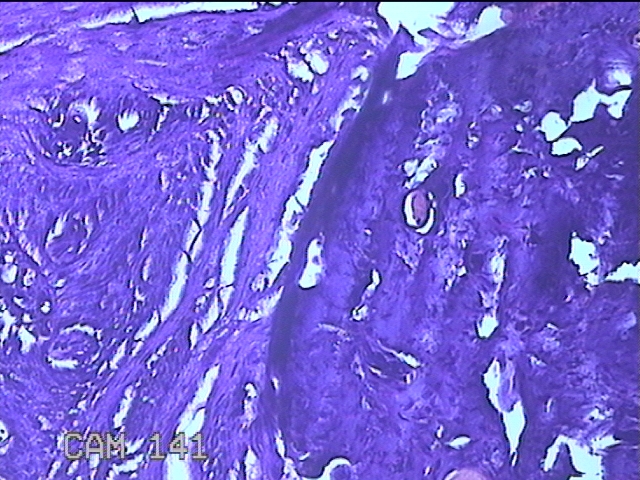

咽部肿物

临床诊断

一般病史

反复咽异物感不适1月。

标本名称

大体所见

灰白粉红色肿物0.8x0.5x0.2cm一个,表面光滑。

图4